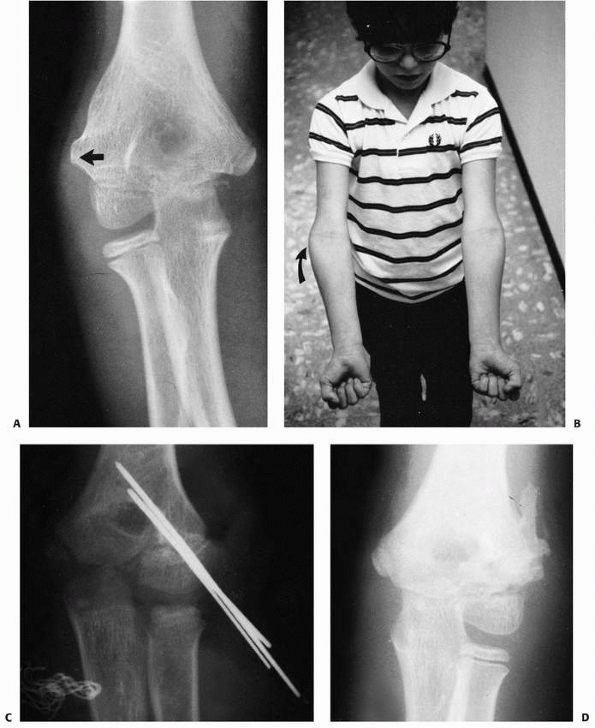

![]() |

FIGURE 15-15 A. A 10-year-old boy with cubitus valgus resulting from a fracture of the lateral condylar physis with nonunion. B.

Nonunion with cubitus valgus. Radiograph showing both angulation and translocation secondary to nonunion of the condylar fragment. |

FIGURE 15-16

Nonunion without translocation. Milch type I fracture pattern. Despite nonunion, elbow stability was maintained because the lateral crista of the trochlea had remained intact (arrow). Valgus angulation also developed. |